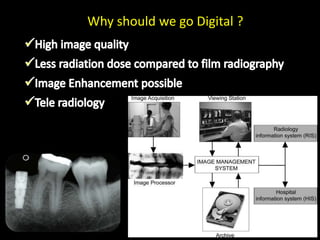

4. Digital radiography provides advantages like automated measurements and image manipulation but has higher initial costs and bulkier sensors.